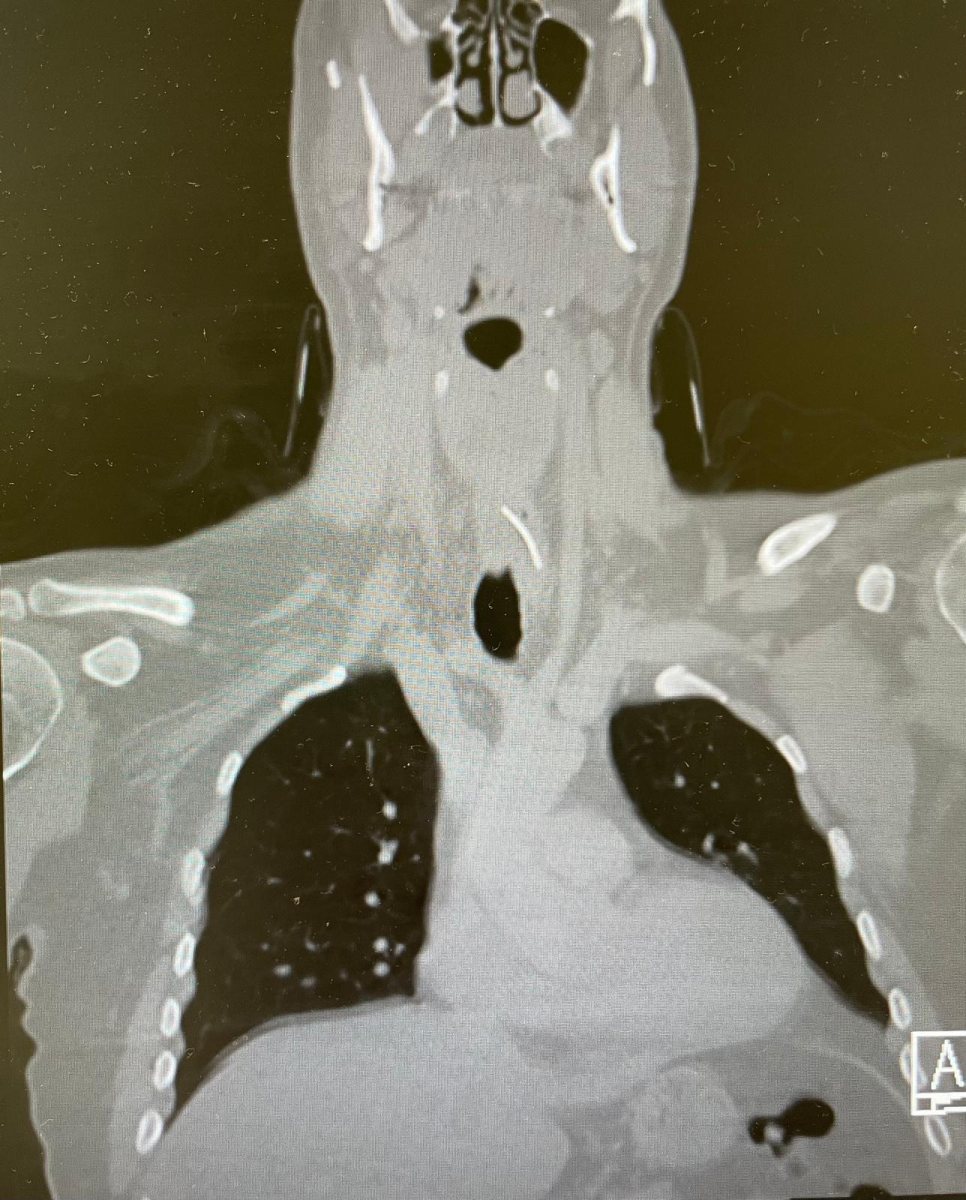

ד"ר אוהד כהן, רופא בכיר ואחראי תחום ניתוחי מיתרי קול וגרון במחלקה, ציין כי "עוצמת הכאב ומשך הזמן שעבר מאכילת הסנדוויץ' היו חריגים, ולכן ביצענו בדיקת CT שהדגימה את הגוף הזר בוושט העליון".

בניתוח האנדוסקופי הדחוף שבוצע דרך הפה, בהובלת ד"ר כהן וד"ר שטריקמן ובליווי רופאי מרדימים, התברר כי מדובר בברזל חד מאוד באורך של שלושה ס"מ, שכבר גרם לפצע בדופן הוושט. ד"ר כהן הדגיש כי "ביצענו ניתוח אנדוסקופי דרך הפה, שלפנו את הברזל שכבר הספיק לגרום לפצע בדופן הוושט. חשוב להבין שכל איחור נוסף היה עלול להוביל לזיהום קשה ולסיבוכים".